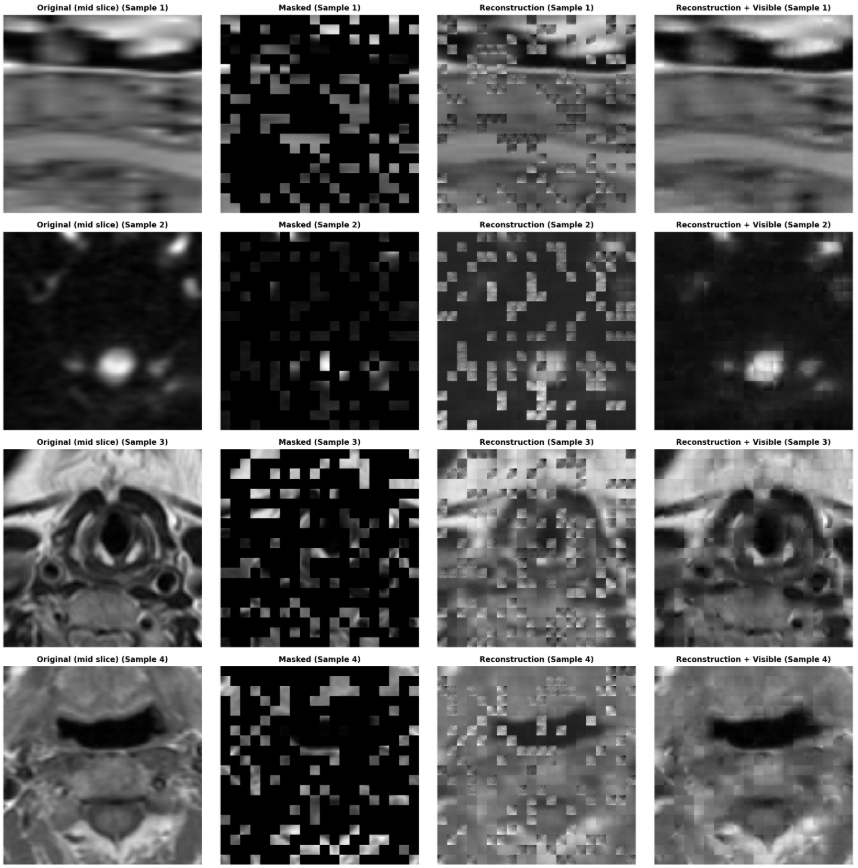

预训练:

训练集:医院+公开,约

800x(3~4)x256x256x801、单模态resize ->

160x160x802、crop -> 0.4 mask -> 0.75

3、mae3d输入,通道改为80,单个patch大小为

160/patch_size,160/patch_size,80/patch_size保存encoder权重。4、encoder输出为

batch_size,160/patch_size x 160/patch_size x 80/patch_size,embed